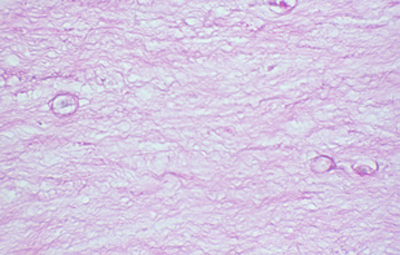

Cuando el examen patológico se realiza en cortes de tejido corneal procesados en parafina, (biopsias y discos de córnea de queratoplastias) las coloraciones que empleamos usualmente son la coloración de Hematoxilina-Eosina (Figura 49), el Blanco de Calcofluor. (Figura 50), la de PAS (Figura 51 y 52). De nuevo, la consideración de que una infección corneal puede ser causada por Acantamoebas es la condición indispensable en el diagnóstico diferencial para llegar a su diagnóstico

Acanthamoeba PAS, Original x160

Fig. 51 PAS, Original x160

Fig. 52 PAS, Original x160